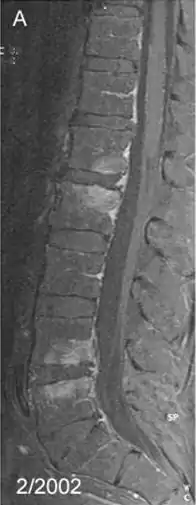

صورة لالتهاب الفقار بالرنين المغناطيسي